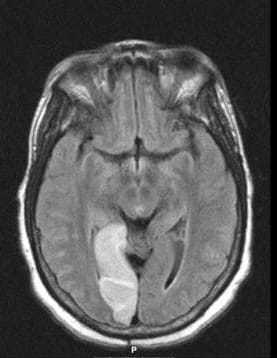

Neuroradiology and PACS NeuroimagingIn addition, one of the major conveniences of the neurology residency training program is the system-wide implementation of the Picture Archiving Communications Systems (PACS) digital imaging system at the University Hospitals.

As soon as a scan is completed, it is immediately available to be reviewed electronically. No longer do residents need to spend time looking for lost films or walking to the radiology department to view scans.

Scans are now easily viewed during conferences and rounds. Large, high-resolution monitors are available on all hospital units. Viewing is also easily performed on any computer monitor in the hospital and outpatient clinic.